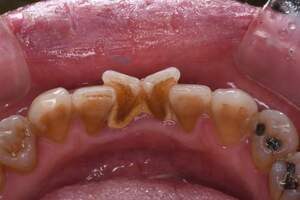

歯石除去

治療前

治療後

| 年齢 | 31歳・女性 |

| 主訴 | 主訴:歯石除去 部位:全顎 |

| 治療内容 | 初診検査・歯石除去 |

| 治療期間 | 2週間 |

| 費用 | 合計:約4,000~5,000円 内訳 初診料:約3,000~4,000円 (保険診療) 歯石除去:約1,000円 (2023年1月現在) |

| リスク・副作用 | ・歯肉の炎症がある場合は歯石除去中に出血を伴う可能性があります。 ・処置後に歯がしみることがあります。 ・歯茎の炎症が軽減すると歯茎が引き締まり、歯が長く見えることがあります。 |

| 治療方針 | 前歯部に叢生(歯列不正)があり多量の歯石が認められました。炎症の抑制を優先するため初診時はTBIのみ行い、2回目以降で歯石除去を行いました。今後は縁下歯石(歯ぐきの中に付着する歯石)の除去を全顎的に行っていく予定です。 |

| 担当者所見 | 叢生(そうせい)とは歯が折り重なるようにデコボコにはえている状態をいいます。歯ブラシが難しく磨き残しをしやすい為、普段使用している歯ブラシに加えワンタフトという細かい部分も磨くことのできる小さな毛束の歯ブラシの使用をおすすめしました。 |

| 担当者所見 | 歯石の存在は感じていたものの歯科医院に苦手意識が強く3年ほど放置していたとのことでした。 舌で触った時にザラザラすることや口臭も気になった為、今回意を決してご来院くださいました。 ブラッシング指導を熱心に聞いてくださり、セルフケアで歯肉の炎症を抑えた上で歯石除去ができたのでお痛みが少なく行えました。 患者様も苦手意識が克服できたと喜んでくださり、今後の治療にも積極的な姿勢です。 |